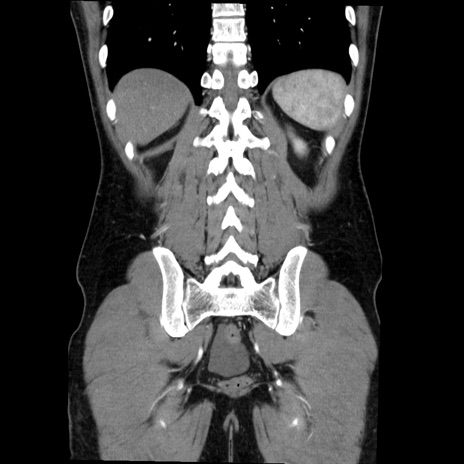

症例36(冠状断像)

【症例】20歳代 男性

【主訴】心窩部痛

【現病歴】今朝より上腹部痛あり。一旦軽快していたが再度出現したため救急要請。昨日夕に白身の魚を含む刺身を食べた。

【身体所見】BP 136/89mmHg、HR 74/min、BT 37.0℃、腹部:膨満、軟、心窩部に圧痛あり。反跳痛なし、筋性防御なし、腸雑音やや亢進あり。

【データ】WBC 17700、CRP 0.48